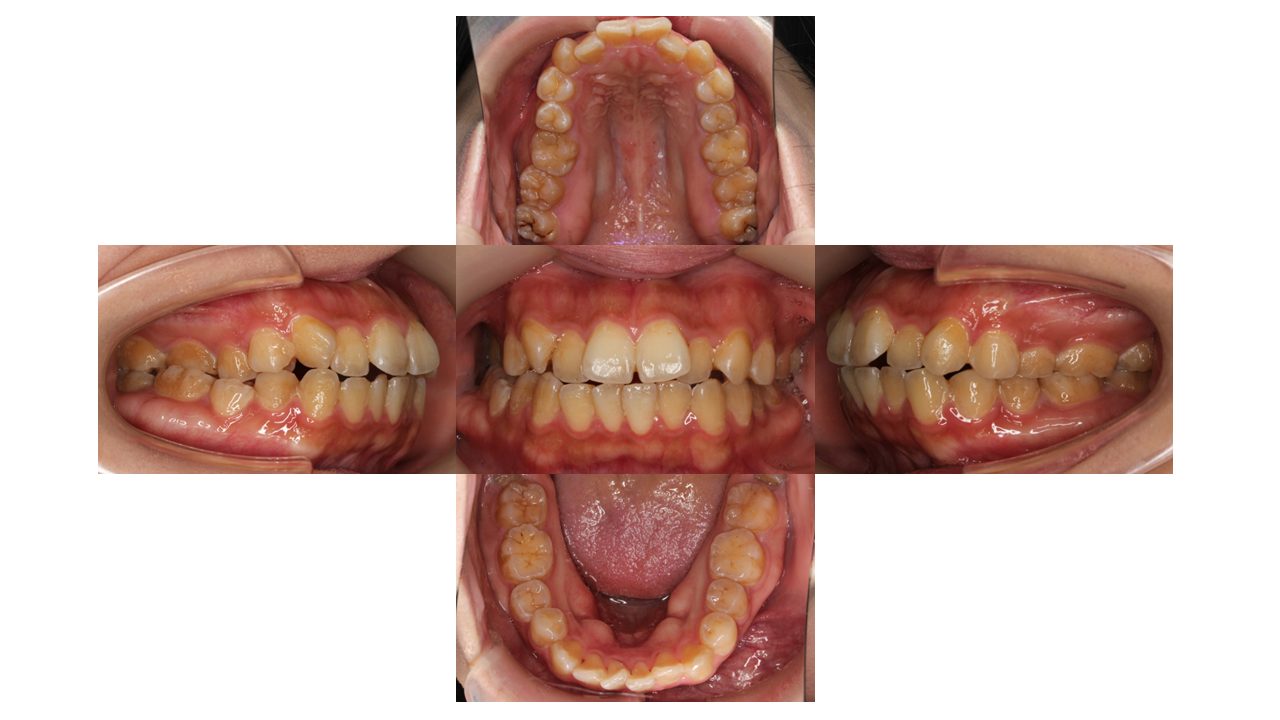

初診時の口腔内の状態です。

前歯の凸凹・口元が出ていることがお悩みでご来院されました。